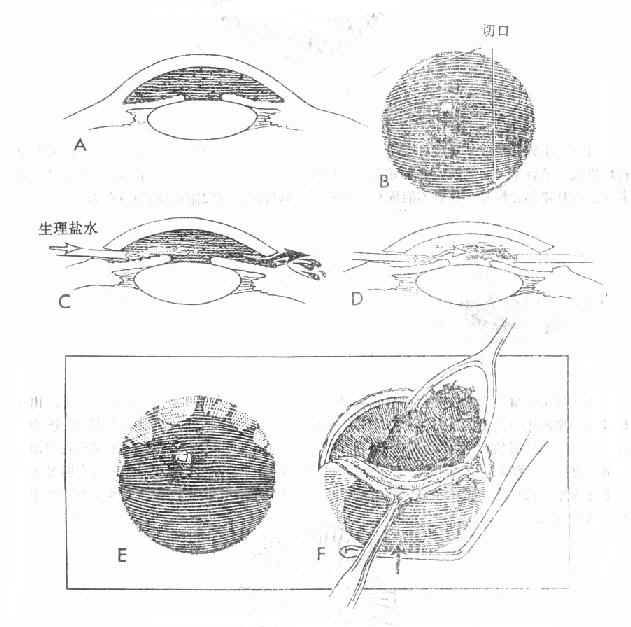

治疗原则:①卧床休息,适当应用镇静剂;取半卧位;②全身应用止血剂,如止血敏、云南白药,可联合应用皮质激素;③可不扩瞳、不散瞳。出现虹膜刺激症状时,可及时散瞳;④注意观察眼压。眼压升高时,应用降眼压药物;⑤每日观察积血吸收情况。积血多、吸收慢,尤其为暗红色、有血块时,伴眼压升高,经药物治疗眼压仍不能控制,应作前房穿刺术放出积血。有较大凝血块时,可切开取出血块。以避免角膜血染(图15-5)。

图15-5 前房积血的手术处理方法。

A-D示前房全出血2日,行前房冲洗吸出术。E-F示陈旧性前房全积血,经角巩膜缘大切口去除凝血块。